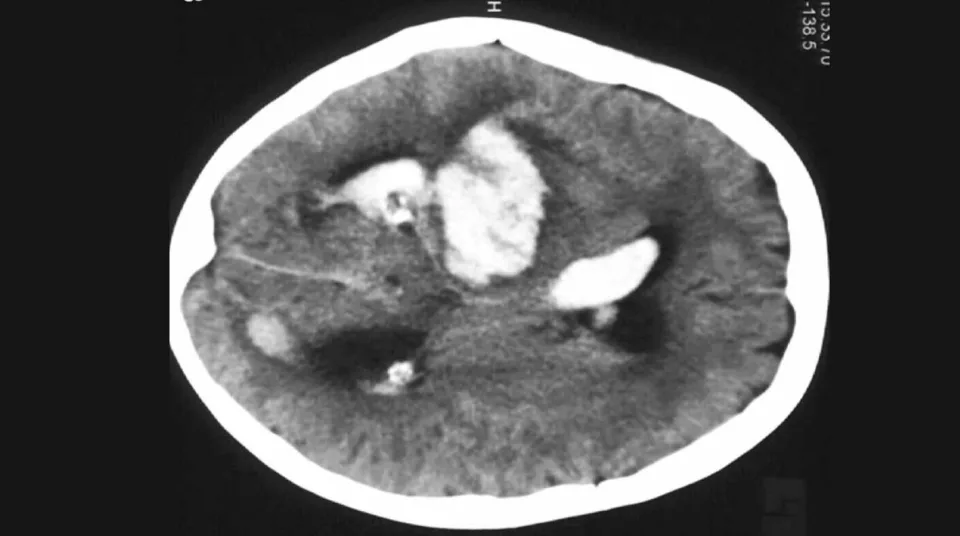

Las principales preguntas de investigación que deben abordarse es comparar con el estándar de atención de rutina, con un programa de atención activa dirigida a un objetivo de manejo que involucra control fisiológico temprano (disminución intensiva de la presión arterial [PA], control glucémico y tratamiento temprano de la pirexia) y reversión de anticoagulación, si esto mejora la recuperación funcional para pacientes que sufren un accidente cerebrovascular agudo debido a hemorragia intracerebral espontánea (HIC).

Dada la naturaleza compleja y grave de la HIC, se requieren pruebas confiables para guiar la entrega y la política de atención médica. Sin embargo, las auditorías de los datos administrativos de hospital sobre accidente cerebrovascular indican un cumplimiento bajo de muchas recomendaciones de Nivel I, especialmente en los LMIC. El ensayo INTERACT2, una iniciativa previa en la que la UDD también participó como Centro de Coordinación Regional para América del Sur, fue un estudio importante que resolvió gran parte de la incertidumbre sobre el manejo de la PA elevada en ICH y, por primera vez, brindó apoyo para una estrategia médica efectiva . Los factores que impiden la transferencia eficiente de fundamentadas investigaciones clínicas, como la de INTERACT2, a la práctica clínica son complejos. La recién iniciada investigación de INTERACT3 tiene como objetivo evaluar la efectividad de implementar un programa de atención con metas cualitativas dirigidas a mejorar la calidad, que incluya el control fisiológico temprano recomendado por la guía (reducción intensiva de la PA, control glucémico y tratamiento de la pirexia) y la reversión de la anticoagulación, en contra de la habitual atención en pacientes con ICH aguda en hospitales.